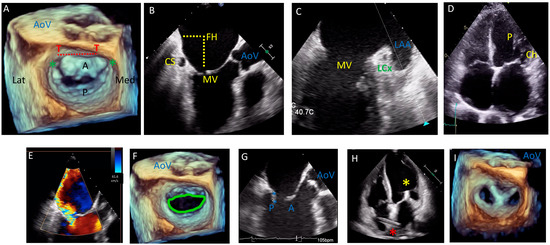

2. Anatomical and Imaging Considerations

3. Echocardiography